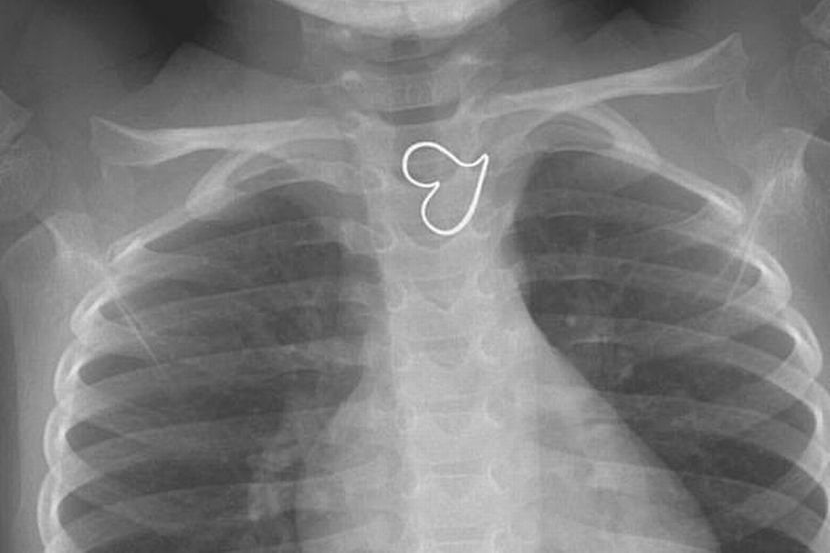

IMBASAN x-ray menunjukkan terdapat 'hati' di bahagian dada seorang budak perempuan berusia tiga tahun.

Kanak-kanak yang tidak dikenal pasti identitinya dari San Diego, California, itu dibawa ke jabatan kecemasan setempat apabila dia tertelan loket rantai.

Imbasan x-ray menunjukkan objek tersebut dalam tiub yang menghubungkan tekak ke perut.

Apa yang mengejutkan, bentuk hati yang jelas dan sempurna dapat dilihat dalam imbasan tersebut.